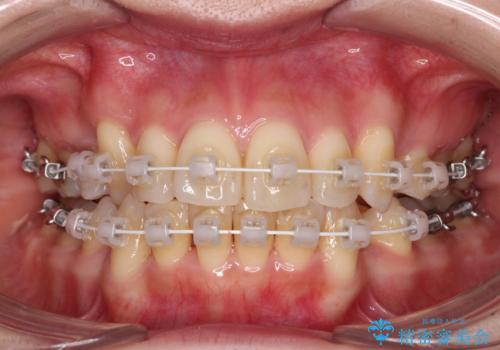

- 矯正装置

- 審美装置

- 治療期間

- 2年2ヶ月